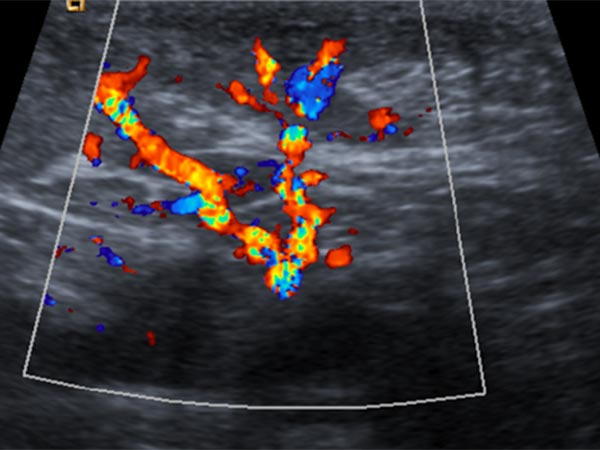

On B-scan ultrasonography (top image), the tumor is relatively homogeneous, hypoechoic, and clearly solid, not compressible. Color-coded duplex ultrasonography (bottom image) shows intense perfusion via multiple arterial vessels. This is suggestive of a congenital vascular tumor and, in this case when combined with the bluish appearance, the special case of a congenital hemangioma.